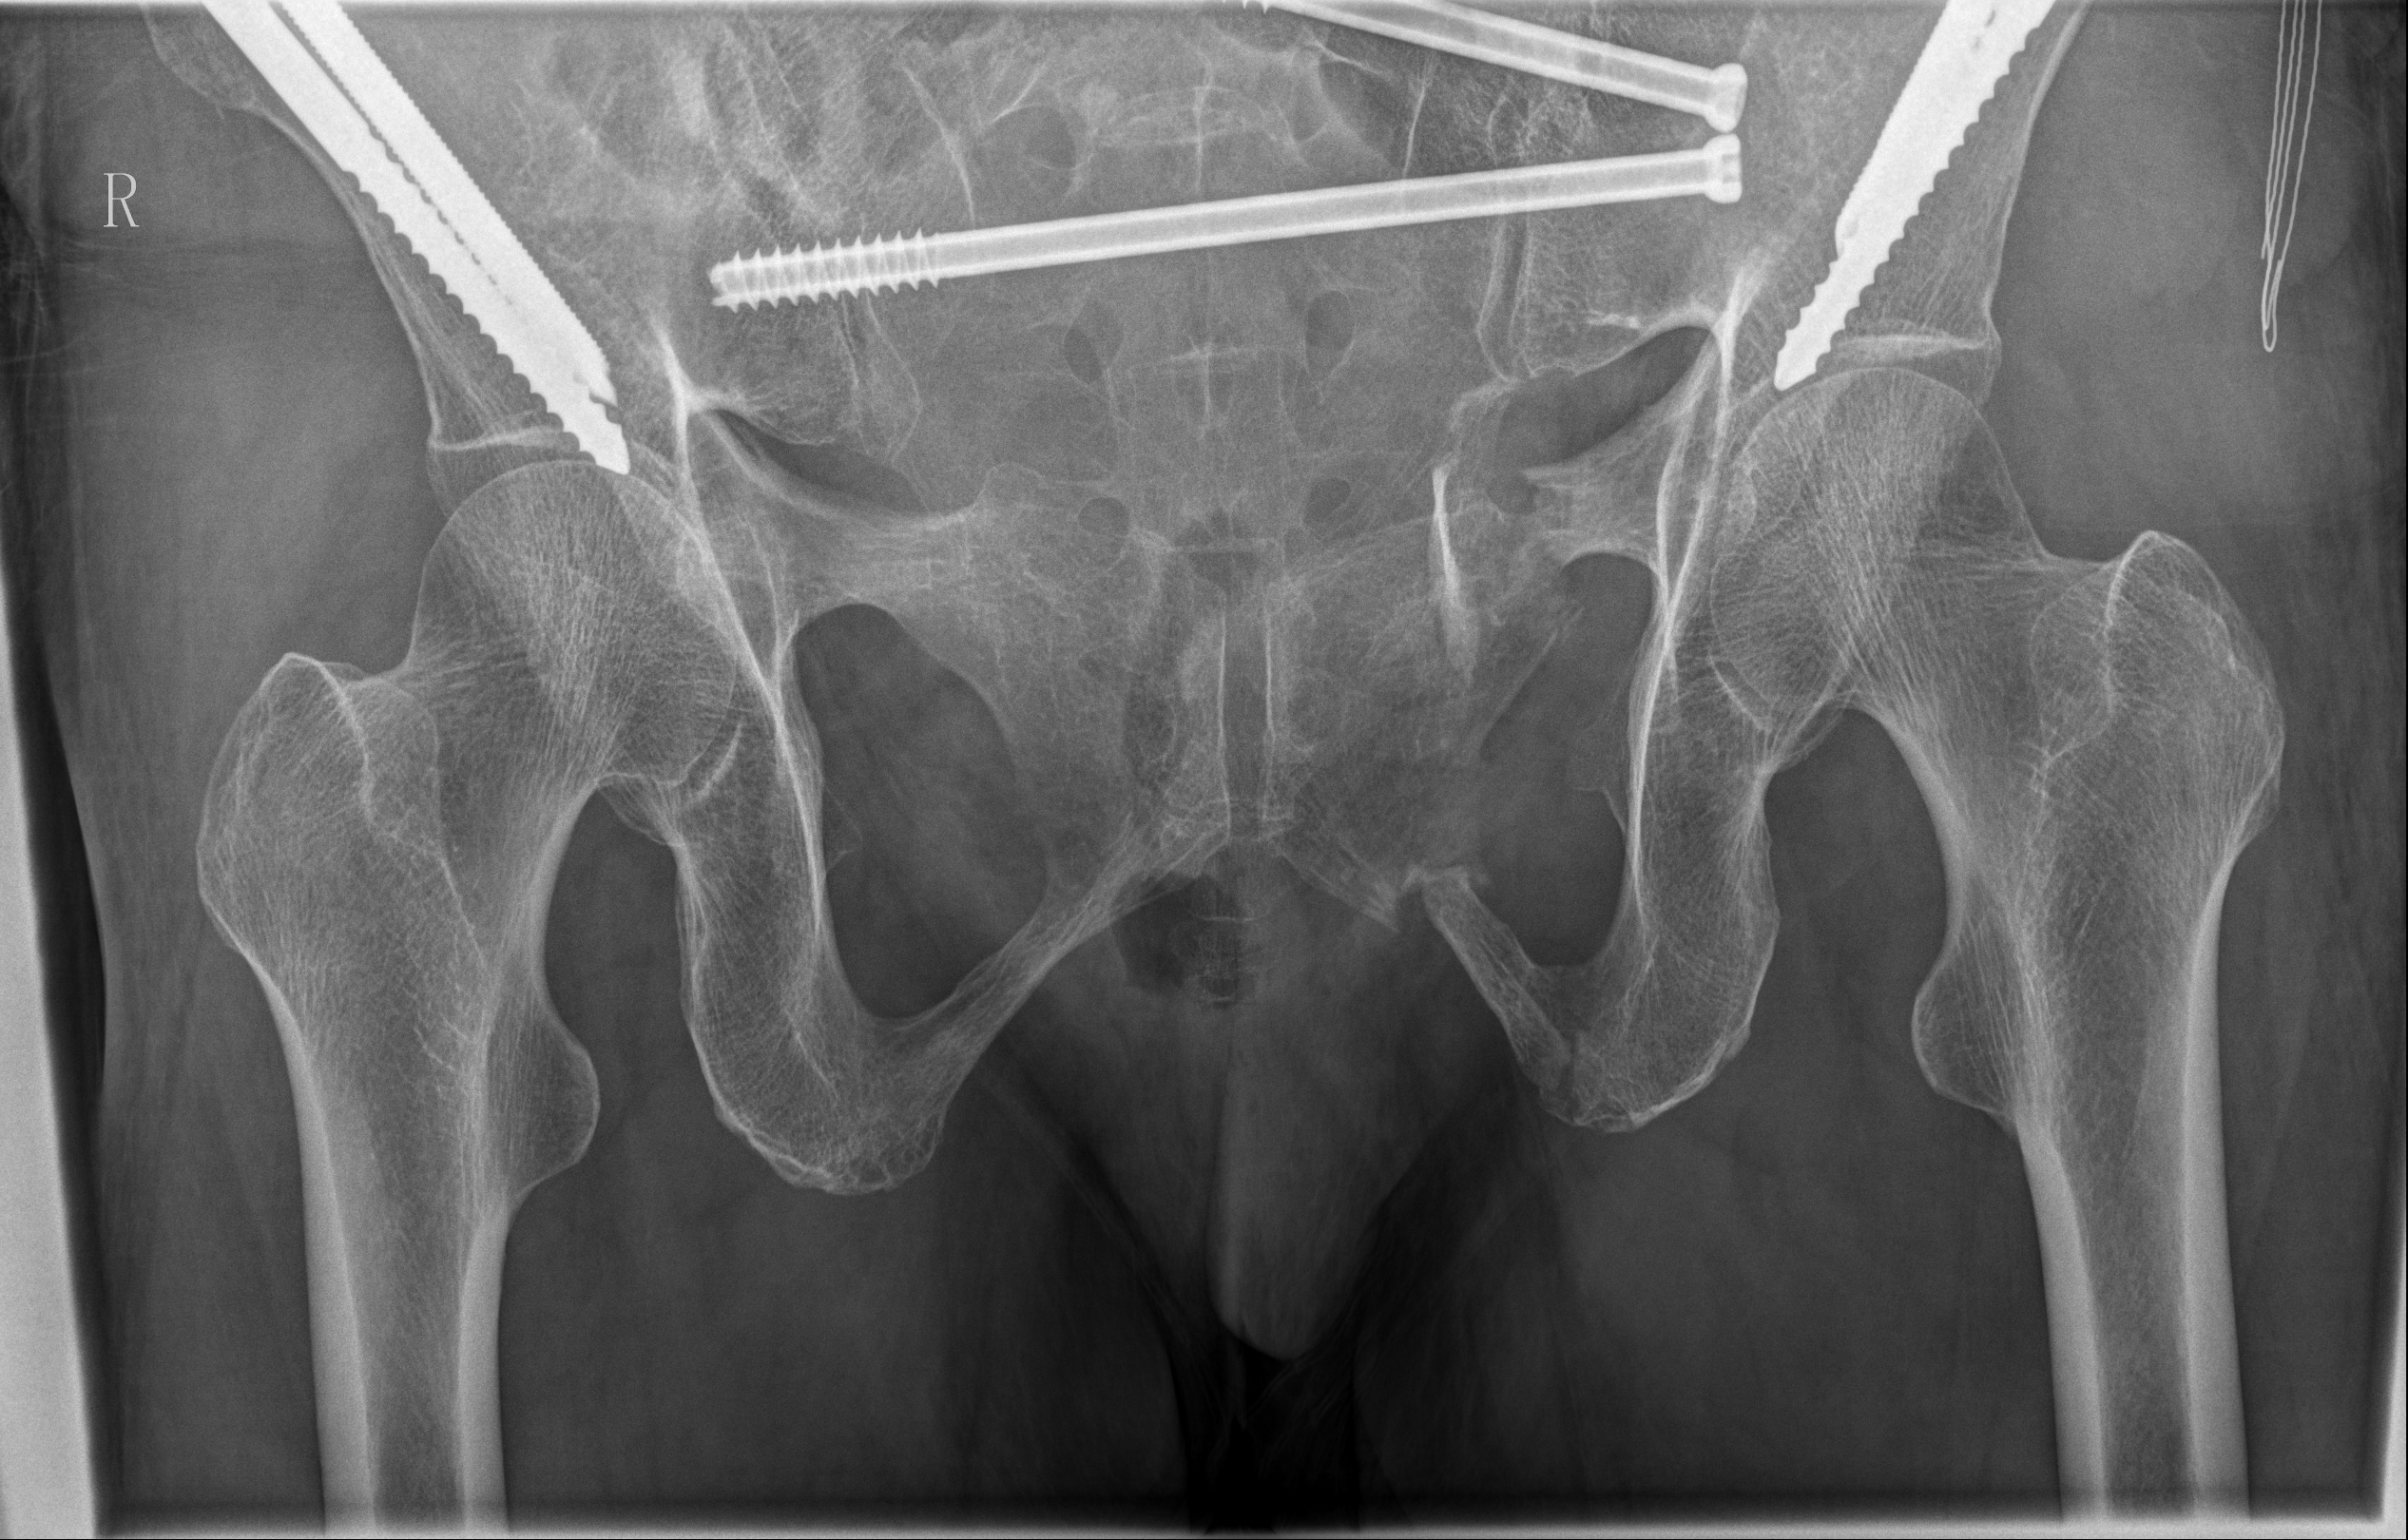

术后骨盆DR片

在手术过程中,骨科手术机器人展现了卓越的性能。通过精确的术前规划和实时的术中导航,医生仅通过几个微小的切口(每个仅1cm长),便成功地置入了2枚骶髂螺钉和4枚骨盆外固定Schanz钉。在骨科手术机器人的辅助下,此次手术时间较传统手术明显缩短,术中失血量仅约20ml,手术创伤小,大大降低了手术风险。值得注意的是,此次手术采用新型的骨盆支架外固定术,该技术可将Schanz钉完全置入髂骨内外板之间并打入髋臼顶相对致密且丰厚的骨质内,使骨盆骨折得到了有效固定,且该技术具有基于触诊、不依赖透视、置钉精准且深入的优势。得益于骨科手术机器人微创手术治疗,该患者在术后3天即顺利出院,体现了现代快速康复理念。骨科手术机器人技术的顺利开展,标志着金瓶梅电影 在数字智能治疗复杂骨盆骨折疾病方面迈入精准微创新高度。